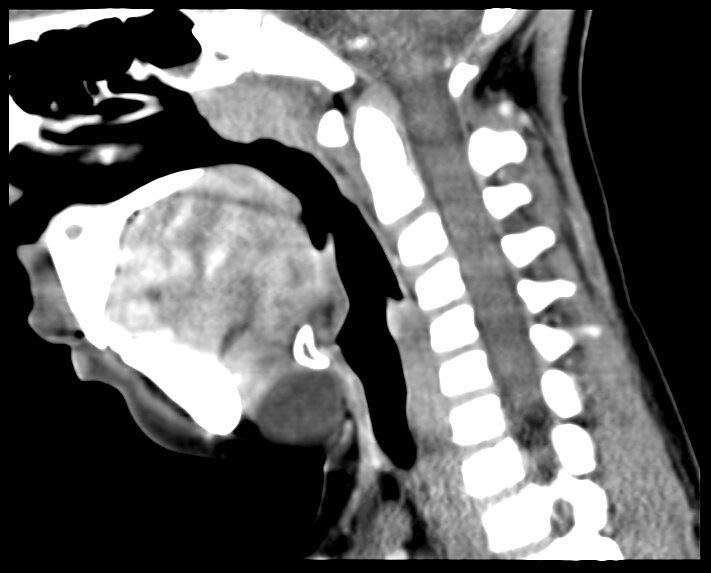

颈前中线或稍偏侧自舌盲孔到甲状腺径路上的任何位置的类圆形或者圆形囊性肿块,低密度、边界清楚、壁薄的囊性肿块,与舌骨相连(图2)。如伴感染或者出血,密度可增高,囊壁可增厚呈不均匀强化。

囊性低密度肿块(白色箭头),大小约2.1*3.1*1.6cm,边缘光滑、边界清、与舌骨(黑色箭头)关系密切。